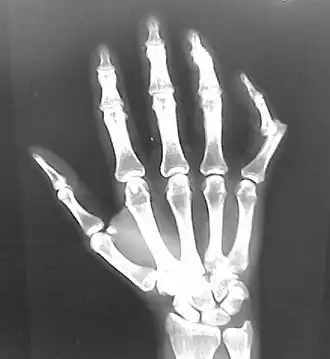

- Finger

- Interphalangeal (IP) or metacarpophalangeal (MCP) joint dislocations[41]

- In the United States, men are most likely to sustain a finger dislocation with an incidence rate of 17.8 per 100,000 person-years.[42] Women have an incidence rate of 4.65 per 100,000 person-years.[42] The average age group that sustain a finger dislocation are between 15 and 19 years old.[42]

- The most common dislocations are in the proximal interphalangeal (PIP) joints.[8]